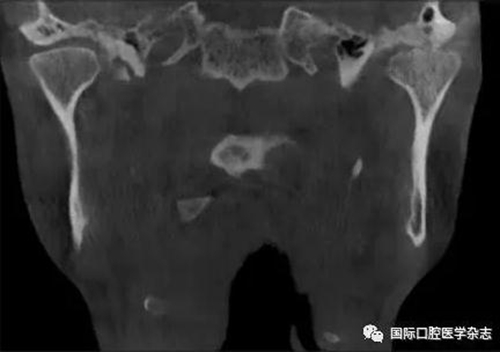

(3)骨關節(jié)?。▓D2):屬于顳下頜關節(jié)器質性改變,主要發(fā)生在髁突的骨質變化,其次是關節(jié)窩及關節(jié)結節(jié)的改變。影像學檢查發(fā)現(xiàn)骨、軟骨和關節(jié)盤有退行性改變,關節(jié)運動時可聞及連續(xù)摩擦音。伴有滑膜炎或關節(jié)囊炎時,有開口痛和咀嚼痛,開口受限,這時可稱骨關節(jié)炎。

圖 2 骨關節(jié)病